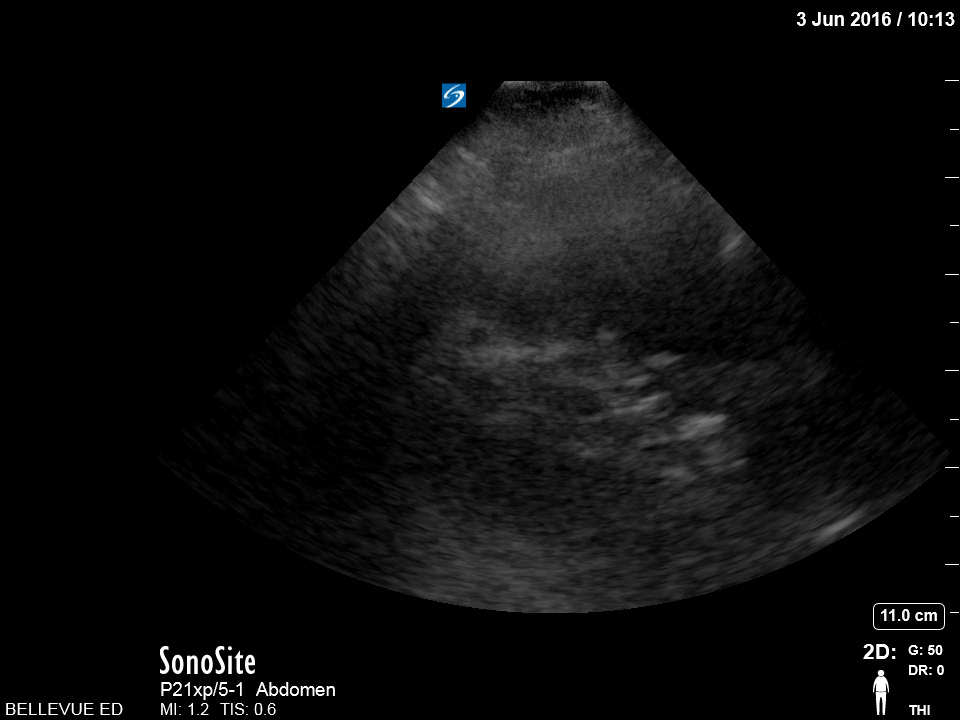

Left Kidney Blue: Cortex, Pink: Medulla, Yellow: Spleen, Green: Spine

https://www.thepocusatlas.com/renal